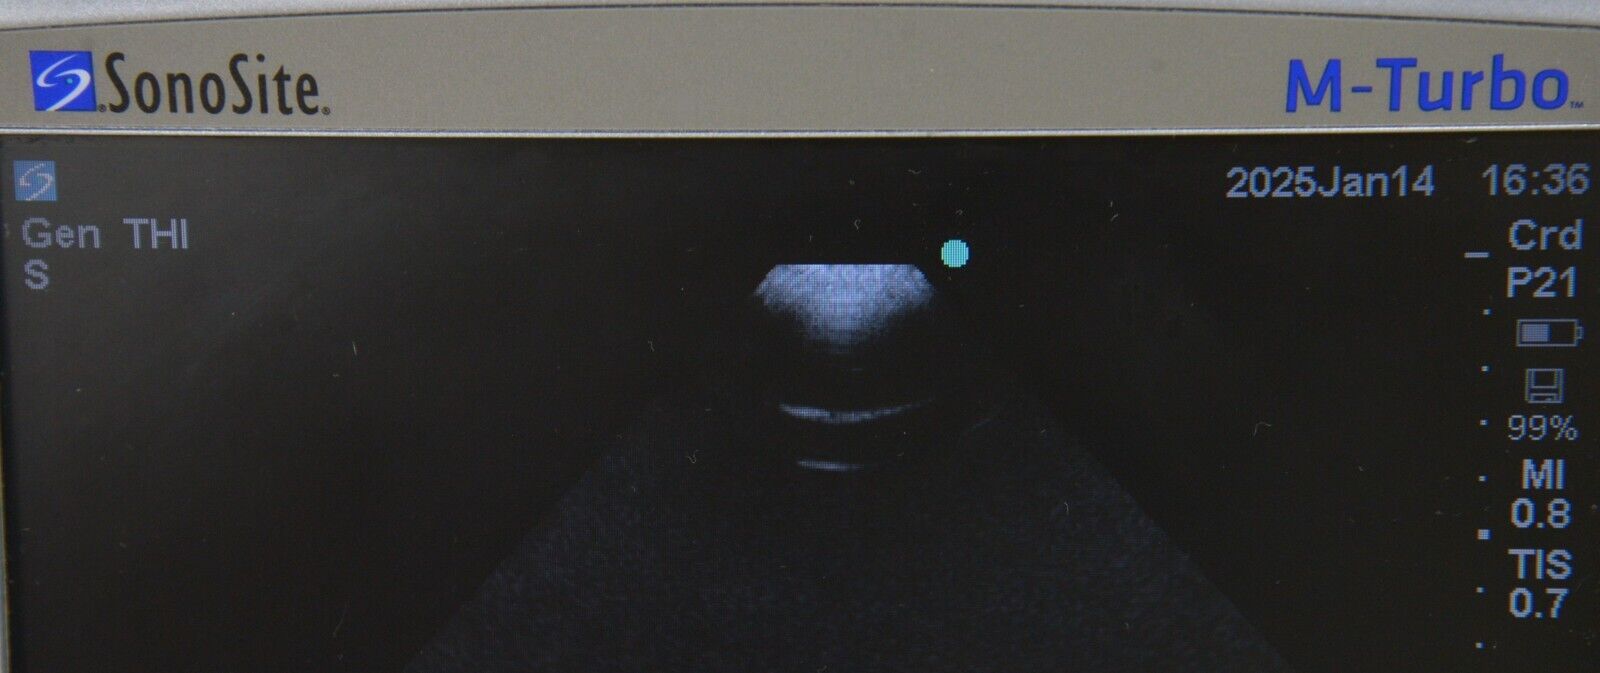

- Fujifilm Sonosite M-Turbo Ultrasound System W/ SonoSite P21x/5-1 MHz Transducer

January 15, 2025Fujifilm Sonosite M-Turbo Ultrasound System W/ SonoSite P21x/5-1 MHz Transducer

Fujifilm Sonosite M-Turbo Ultrasound System W/ SonoSite P21x/5-1 MHz Transducer

This Fujifilm Sonosite M-Turbo Ultrasound System W/ SonoSite P21x/5-1 MHz Transducer is in good working condition. This unit powers on properly and the display screen produces a clear picture. The buttons respond properly to selection and the connections are clean and in good condition. The battery holds a charge. There are a few minor scuff marks from previous use (see photos). This item comes with a 30 day satisfaction guarantee. Includes everything displayed in the photos and nothing else.